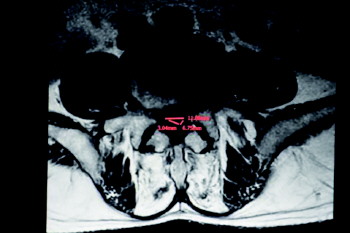

提起开刀手术,王先生就忐忑不安。想到四年前儿子“腰椎间盘突出”就是被林主任给治好的,就抱着极大的希望再次找到了林主任。接诊后,林主任立即为他做了专科查体,并进行了腰椎核磁和CT检查。检查发现,王先生的腰椎管巨大突出处于L4/5,正好压迫着腰部神经根组织,并且椎管内增生狭窄严重,这也是他病情发展迅速、疼痛加重的根源所在。